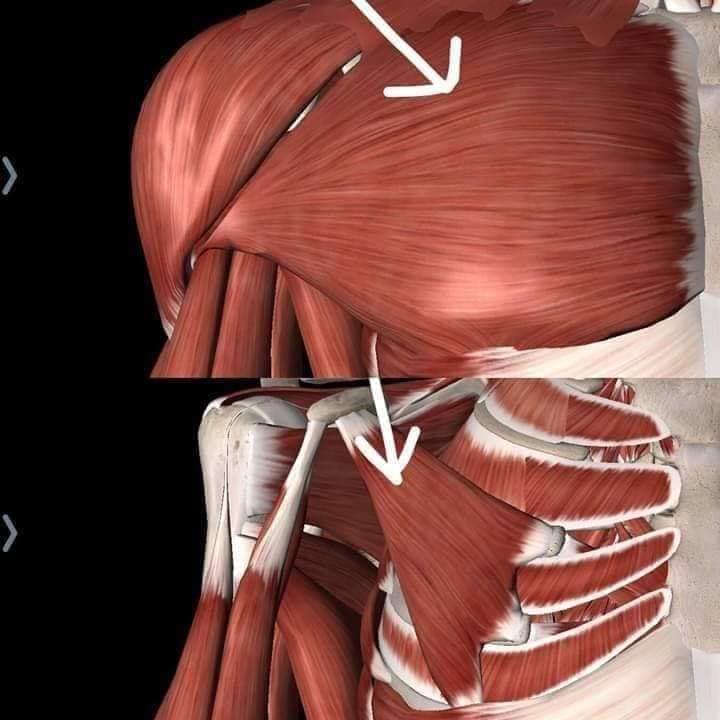

М'язи, що піднімають лопатку: Трапецієподібний м'яз: великий м'яз, що покриває верхню частину спини. Його функція - підтримка і рух лопаток, а також забезпечення стабільності хребта.

М'язи, що ведуть лопатку до хребта: Широкий м'яз спини: великий м'яз, що розташований в нижній частині спини. Він відповідає за рухи плечей і лопаток, а також за розширення верхньої частини тулуба.